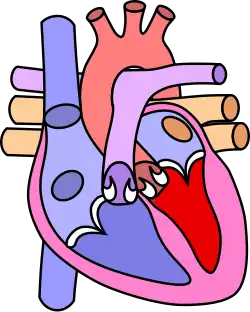

Diagram of a healthy heart and one with tetralogy of Fallot

Four malformations

"Tetralogy" denotes four parts, here implying the syndrome's four anatomic defects.[2] This is not to be confused with the similarly named teratology, a field of medicine concerned with abnormal development and congenital malformations (including tetralogy of Fallot). Below are the four heart malformations that present together in tetralogy of Fallot:

Heart with tetralogy of fallot A: Pulmonary stenosis; B: Overriding aorta; C: Ventricular septal defect (VSD); D: Right ventricular hypertrophy

Normal heart

Pulmonary Infundibular Stenosis A narrowing of the right ventricular outflow tract. It can occur at the pulmonary valve (valvular stenosis) or just below the pulmonary valve (infundibular stenosis).[4] Infundibular pulmonic stenosis is mostly caused by the overgrowth of the heart muscle wall (hypertrophy of the septoparietal trabeculae),[42] however, the events leading to the formation of the overriding aorta are also believed to be a cause. The pulmonic stenosis is the major cause of the malformations, with the other associated malformations acting as compensatory mechanisms to the pulmonic stenosis.[43] The degree of stenosis varies between individuals with TOF and is the primary determinant of symptoms and severity. This malformation is infrequently described as sub-pulmonary stenosis or subpulmonary obstruction.[44]

Overriding aorta An aortic valve with biventricular connection, that is, it is situated above the ventricular septal defect and connected to both the right and the left ventricle. The degree to which the aorta is attached to the right ventricle is referred to as its degree of "override." The aortic root can be displaced toward the front (anteriorly) or directly above the septal defect, but it is always abnormally located to the right of the root of the pulmonary artery. The degree of override is extremely variable, with 5–95% of the valve being connected to the right ventricle.[42]

Ventricular septal defect (VSD) A hole between the two bottom chambers (ventricles) of the heart. The defect is centered around the most superior aspect of the ventricular septum (the outlet septum), and in the majority of cases is single and large. In some cases, thickening of the septum (septal hypertrophy) can narrow the margins of the defect.[42]

Right ventricular hypertrophy The right ventricle is more muscular than normal, causing a characteristic boot-shaped (coeur-en-sabot) appearance as seen by chest X-ray. Due to the misarrangement of the external ventricular septum, the right ventricular wall increases in size to deal with the increased obstruction to the right outflow tract. This feature is now generally agreed to be a secondary anomaly, as the level of hypertrophy tends to increase with age.[45]